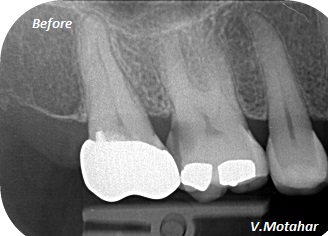

Root canal treatment on three rooted tooth! which had 4 canals!